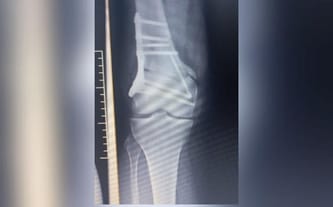

Przed nami kolejne leczenie, zabiegi, operacje, konsultacje ze specjalistami oraz dalsza diagnostyka. Ostatnia reoperacja (17.05.) odbyła się planowo. Po wcześniejszej operacji (22.03.) w dalszym ciągu pozostały poważne komplikacje w postaci braku zrostu w kości udowej. Co więcej, od strony zewnętrznej zespolenie zsunęło się, co konfliktuje z maziówką w wyniku czego ponownie wbijają się w nogę trzy gwoździe, powodując okropny ból.

Tak było kolejny raz z ostatnia operacją Patrycji (22.03), która niestety zakończyła się dużymi powikłaniami. W ich wyniku doszło do silnego zakażenia oraz pęknięcia kości udowej. Kiedy nasza przyjaciółka uporała się z zakażeniem, to okazało się, że kawałek ostrej śruby przedostał się poza kość i rani jej tkanki miękkie.

Obecnie Patrycja zmaga się z licznymi powikłaniami po operacji nogi wykonanej w ramach NFZ w sierpniu 2022 roku. Operacja z niewiadomych przyczyn - została wykonana tylko częściowo, niezgodnie z wcześniejszymi zaleceniami, wynikającymi ze skierowania. Po ostatniej konsultacji i diagnostyce okazało się, że noga ta wymaga natychmiastowej reoperacji oraz rekonstrukcji, aby można ją było uratować.